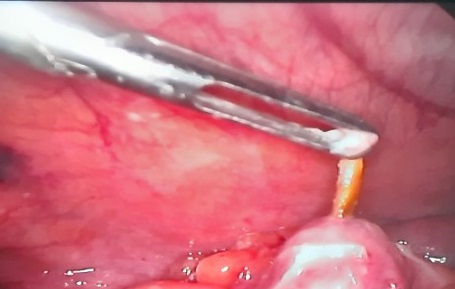

Bệnh nhân vào viện trong tình trạng đau bụng lâm râm 2 ngày. Qua thăm khám lâm sàng thấy có khối u ở vùng hạ sườn trái. Kết quả siêu âm và chụp CT-scnaner cho thấy có dị vật cản quang cùng mạn sườn trái tạo ổ áp xe, phù nề mô mềm xung quanh. Bệnh nhân được chẩn đoán: dị vật ổ phúc mạc nghi do xương cá. Sau khi tiến hành hội chẩn, các bác sỹ đã chỉ định phẫu thuật lấy dị vật.Trong quá trình tiến hành phẫu thuật, kiểm tra thấy mạc nối lớn viêm dính chặt thành một khối vào thành bụng trước trên bên trái, tiến hành gỡ dính, cắt bỏ phần mạc nối lớn viêm dính, lấy ra mảnh xương cá dài khoảng 4cm. Hiện tại sau 6 ngày hậu phẫu, tình trạng bệnh nhân ổn định.

Trong trường hợp này phẫu thuật lấy bỏ di vật và dẫn lưu ổ áp xe là cần thiết nếu không ổ áp xe sẽ vỡ gây viêm phúc mạc hoặc dị vật có thể di cư đến bất cứ vị trí nào khác trên cơ thể.

Một trường hợp thủng ruột do xương gia cầm được phẫu thuật

tại BVĐK Quảng Trị